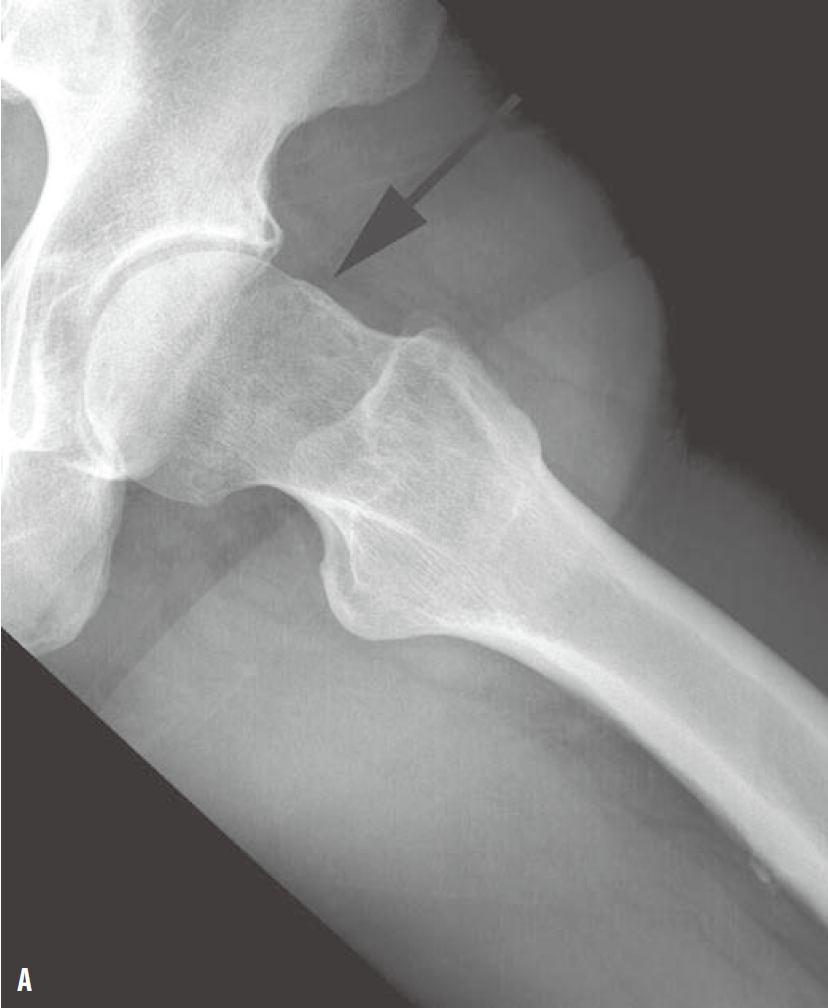

髓关节撞击综合征(femoroacetabular-impingement,FAI)是引起髋关节疼痛及髋关节进行性退行性变的一种常见病因。一般采用骨盆X线前后位照片筛查。骨盆照片时X线中心线应对准尾骨中心及耻骨联合,以保证骨盆不旋转。FAI主要分为3种类型:凸轮型、钳型和混合型。混合型FAI同时具有凸轮型和钳型的异常。凸轮型是股骨头颈连接处形成/发育异常所致,表现为股骨头颈连接处骨性隆起或“枪柄样”改变(缺乏正常的凹度)(图1)。钳型FAI表现为髋臼覆盖或位置异常,可根据在X线平片上见到深髋臼、髋臼前突或髋臼后倾的表现而诊断。深髋臼及髋臼前突X线表现为股骨头及髋臼相对髂骨坐骨线位置异常(图2)。髋臼后倾表现为交叉征、髋臼后壁征、坐骨棘突出征(图3)。

图1 左髋关节蛙式侧位X线片(A)显示股骨头、颈连接处异常隆起(箭),该骨质异常可引起凸轮型FAI。右髋关节前后位X线片(B、C)显示“枪柄样”畸形,其中旋转90°后的前后位X线片(C)可更直观地显示肌骨近端及股骨头所形成的“旧式手枪枪把”样外观